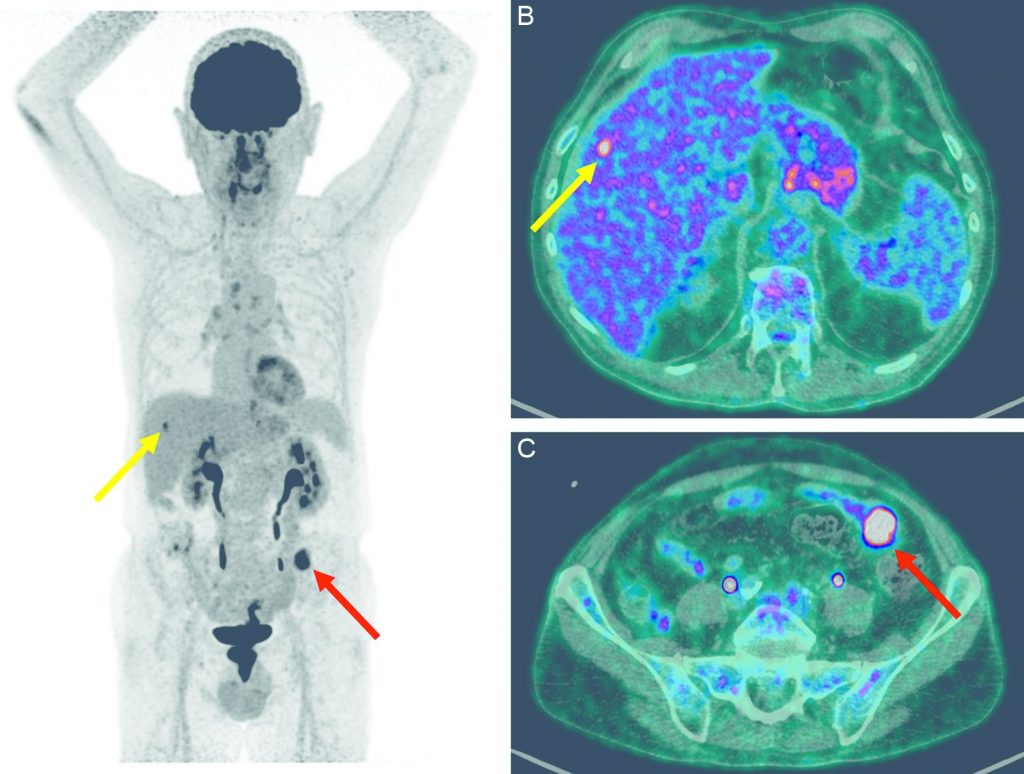

La TEP-TDM au 18FDG est indiquée s’il existe des anomalies suspectes de métastases notamment au niveau hépatique ou dans le contexte de métastases connues et résécables, afin de s’assurer de l’absence d’autres sites métastatiques (figure 15.2).

Fig. 15.2. Images TEP au 18FDG en MIP (A) et fusionnée à la TDM en coupes axiales (B, C) réalisées dans le cadre du bilan d’extension d’un adénocarcinome colique, montrant la localisation primitive (flèches rouges) et une hyperfixation pathologique intrahépatique en rapport avec une localisation métastatique (flèches jaunes).

Source : CERF, CNEBMN, 2022.